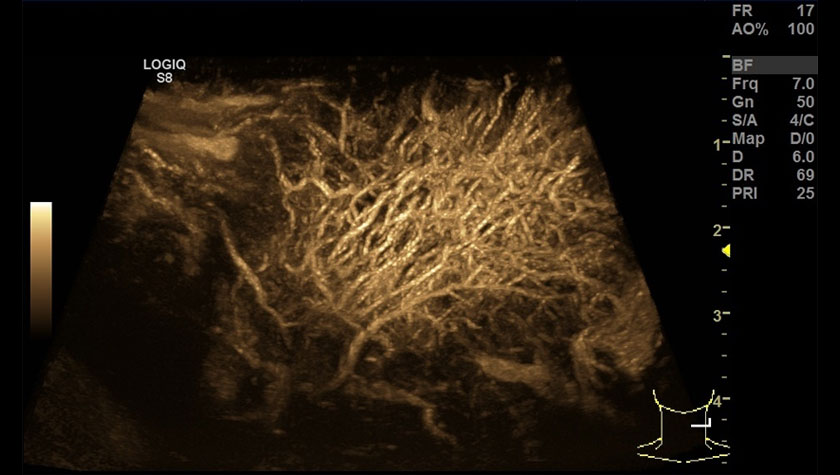

- Режим B-flow – оценивает гемодинамику во всех типах сосудов: от крупных кровеносных сосудов, например, сонной артерии, до мелких сосудов паренхиматозных органов.

- B-Flow — Технология для высокоточной визуализации гемодинамики;

Мозг новорожденного в режиме B-FLOW, датчик 10C-D

Сосудистая сеть шейного лимфоузла, УЗИ с контрастами (CEUS) + B-FLOW, датчик 9L-D